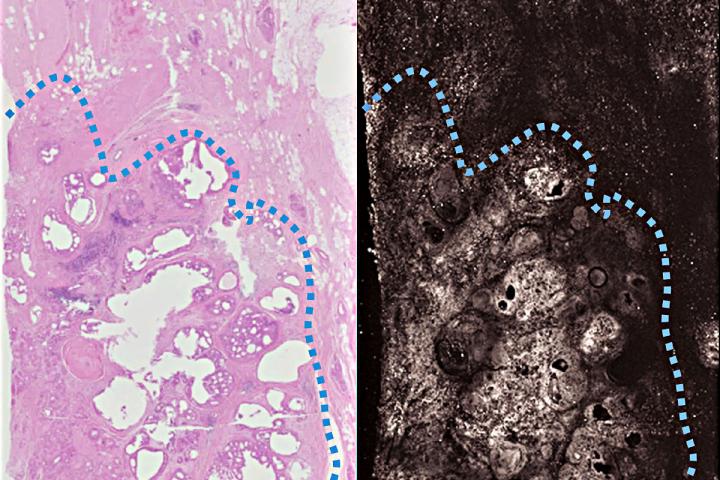

The researchers tested their technique by scanning slices of tumors removed from three breast cancer patients. For comparison, they also stained each specimen according to standard procedures.

The photoacoustic image matched the stained samples in all key features. The architecture of the tissue and subcellular detail such as the size of nuclei were clearly visible.

"It's the pattern of cells - their growth pattern, their size, their relationship to one another - that tells us if this is normal tissue or something malignant," Novack said. "Overall, the photoacoustic images had a lot of the same features that we see with standard staining, which means we can use the same criteria to interpret the photoacoustic imaging. We don't have to come up with new criteria."